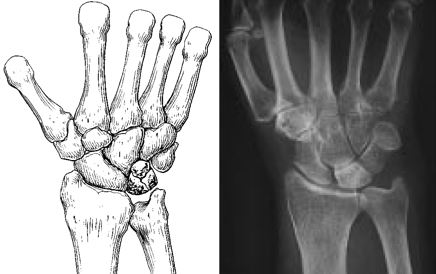

Popular topics On the part of the bodyFeaturedPatellofemoral Pain syndrome Broken neck fracture (broken collar)Public themes by the body Knee ArthroscopyTotal Hip ReplacementPopular Thematics By Part of the Body Activities After Kneeator Cuff and Shoulder Conditioning ProgramPopular Themes By BodyFeoneturedA Safety Guide Your best health. Diseases " Highlights Treatment of Popular Themes Popular Theme Recovery Popular Themes Maintain HealthyFeaturesPopulers PrintEmailFacebookTwitterKienböck's DiseaseKenböck's disease is a condition where the blood supply is interrupted to one of the small bones of the wrist, the lunatic. The bone is living tissue that requires a regular supply of blood to nourish. If the blood supply to a bone stops, the bone can die. This is called osteonecrosis. The damage to the lunatic causes a painful and rigid wrist and, over time, can lead to arthritis. Because the cause of Kienböck's disease is not known. Many people with Kienböck's disease think they have a sprained wrist at first. They may have experienced some form of wrist trauma, like a fall. This type of trauma can interrupt blood flow to the lunatic. Some things may put you at greater risk for the disease. For example, most people have two glasses that supply blood to the lunatic, but in some people there is only one source. This can delay blood flow to the bone. Also, if the two bones of the forearm (the radio and ulna) are different lengths, you can press extra to the lunatic during some wrist movements. Over time, this extra stress on the bone can lead to Kienböck disease. SymptomsThe most common symptoms of Kienböck's disease include: Medical Exam Kienböck's disease is a condition that progresses slowly, and many people don't decide to see a doctor until they have experienced symptoms for several months, perhaps more. During your first appointment, your doctor will discuss your symptoms and medical history, and then examine your hand and wrist. In its early stages, Kienböck disease may be difficult for your doctor to diagnose because the symptoms are so similar to those of a sprained wrist. Imaging tests, such as X-rays and MRI images, are used to confirm a diagnosis of Kienböck disease. Kienböck disease progresses through four stages of gravity. If you are diagnosed with Kienböck disease, your doctor will plan your treatment based on several factors, which is more important, the stage of your progression. Stage 1During the first stage of the disease, the symptoms are similar to those of a wrist sprain. Although the blood supply to the lunatic has been interrupted, X-rays may appear normal or suggest a possible fracture. An MRI analysis can better detect blood flow and is useful for making diagnosis at this early stage. Stage 2The lunar bone begins to harden due to lack of blood supply during Stage 2. This hardening process is called sclerosis. In addition, the lunatic will appear brighter or whiter in X-ray areas, indicating that the bone is dying. To better assess the condition of the lunatic, your doctor may also order MRI scanners or CT scans. The most common symptoms during this stage are wrist pain, inflammation and sensitivity. Stage 3In the third stage, the dead lunar bone begins to collapse and break into pieces. As the bone begins to break, the surrounding bones can begin to change the position. During this stage, patients often experience growing pain, weakness in grip and limited wrist movement. Stage 4If the condition progresses to Stage 4, the surfaces of the bones surrounding the lunatic also deteriorate, and the wrist can become arthritic. Treatment Although there is no complete cure for Kienböck disease, there are several non-surgical and surgical options to treat it. Treatment goals are to relieve pressure on the lunatic and try to restore blood flow inside the bone. Related Articles Wrist Arthritis Wrist Sprains Non-surgical Treatment In the very early stage of the disease, pain and inflammation can be given with anti-inflammatory drugs, such as aspirin or ibuprofen. Doll immobilization for a period of time can help relieve pressure on the lunatic, and your doctor may recommend spine or casting for 2 to 3 weeks. It is important to monitor any changes in your symptoms during the early stage of Kienböck disease. If the pain is not relieved with simple treatments or returns, the doctor may recommend surgery. Surgical Treatment There are several surgical options to treat Kienböck disease. The choice of the procedure will depend on several factors, in particular to what extent the disease has progressed. Additional factors to consider are the patient's level of activity, personal objectives and the surgeon's experience with the procedures. Revascularization. In some cases, it may be possible to return the blood supply to the lunar bone. This procedure is called revascularization. It is more successful during the early stages of the disease—stages 1 and 2—before the lunatic has deteriorated significantly. Revascularization involves the removal of a portion of bone with attached blood vessels from another bone — most of the time a bone from the forearm (radius) or an adjacent bone in the hand. This piece of bone with its blood supply is called vascularized graft. It is inserted into the lunar bone. To help the bones remain in place during healing, an external fixer can be temporarily applied. This is a metallic device attached to the outside of the wrist with nails inserted into the bones. It can relieve pressure on the lunatic while the graft is healing and restoring a blood supply. Joint leveling. If the two bones of the lower arm are not of the same length, a joint leveling procedure may be recommended. Bones can be made longer using bone grafts or shortened by removing a section of the bone. This leveling procedure reduces the forces that compress the lunatic and often stops the progression of the disease. Approximate line spectomy. If the lunatic collapses severely or breaks into pieces, it can be eliminated. In this procedure, the two bones on each side of the lunatic are also eliminated. This procedure, called proximal row carpectomy, will relieve pain while maintaining partial wrist movement. (Left) The three wrist bones that are removed in a proximal row carpectomy are shaded here. (Right) An X-ray image of a wrist after a proximal row carpectomy. Fusion. To relieve pressure on the lunatic, the nearby bones of the wrist can be merged together to make a solid bone. A fusion can be partial, in which only some of the bones are merged. This procedure relieves pain and retains some wrist movement. If the disease has progressed to severe wrist arthritis, fusing all wrist bones to the radio will relieve pain and improve the hand function. Although the whole wrist movement is eliminated in a complete fusion, the rotation of the forearm is preserved. In a fusion, the bones of the wrist are held along with a plate, screws and pins. ResultsThe disease of Kienböck varies considerably in its severity, as well as its rate of progression. Each patient's response to treatment depends on the degree of damage to the bones of the lunar and surrounding wrist. Some patients may require more than one procedure if the disease continues to progress. In short, patients with Kienböck disease should not expect to return to normal wrist function after any treatment. However, treatment provides the greatest opportunity for long-term preservation of function and pain relief. Last revision May 2012 Contributed Updated byPeer-Reviewed byAAOS does not support any treatment, procedures, products or doctors referred here. This information is provided as an educational service and is not intended to provide medical advice. Anyone looking for specific orthopedic advice or assistance should consult your orthopedic surgeon, or locate one in your area through the AAOS program on this website. Copyright ©1995-2021 by the American Academy of Orthopaedic Surgeons. All material on this website is protected by copyright. All rights reserved. This website also contains copyrighted material by third parties.